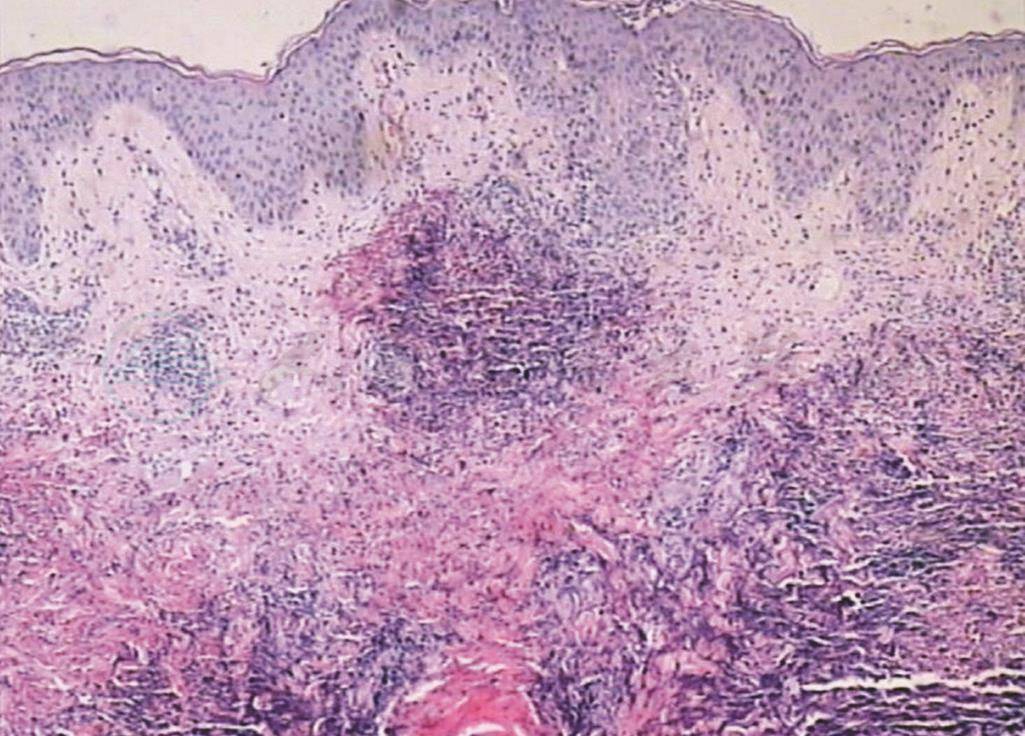

组织病理:网篮状角层,一处角层下小水疱,疱内为嗜酸性粒细胞及多形核白细胞。表皮肥厚,表皮内海绵水肿,乳头区水肿,乳头区血管扩张、充血。真皮全层片状坏死灶,有多数嗜酸性粒细胞及中性粒细胞浸润,嗜酸性粒细胞脱颗粒和变性,嗜酸性物质和核尘沉积在胶原纤维上形成“火焰样图像”。病理符合嗜酸性粒细胞增多性蜂窝织炎(图2~5)。

图2 表皮肥厚,真皮全层片状坏死灶(HE染色×40)